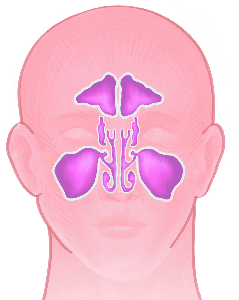

Detailreiche Fotografien aus der medizinischen Praxis ergänzen die Texte; moderne, genaue,

wissenschaftliche Zeichnungen geben Einblick in die Anatomie und die Funktion der Lunge und

anderer Organe.